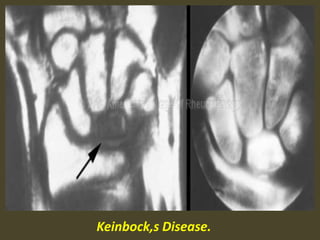

Keinbock,s Disease.